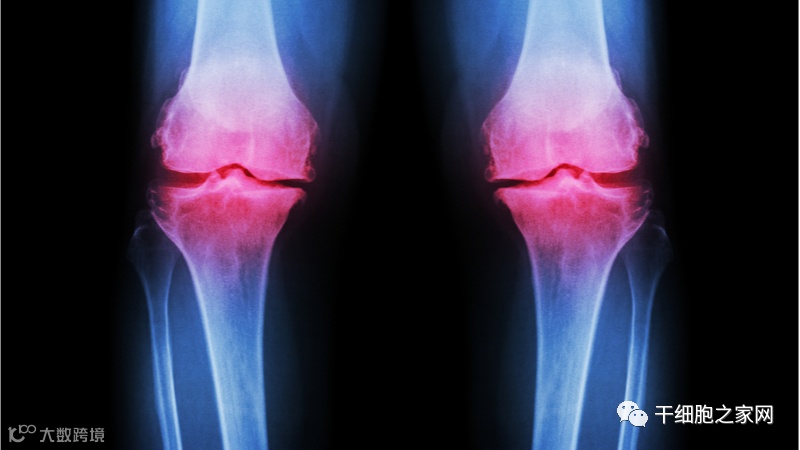

骨关节炎(OA)是与年龄有关的疾病。患者为中老年人居多,毫不夸张的说它影响了全球65岁以上一半以上人口数量。OA由于自身的摩擦和与年龄相关的细胞功能障碍,导致关节软骨退化。OA本身并不危及生命,其与一般死亡率的关系的报告尚无定论[2],但它可能引起极大的不适甚至残疾,从而困扰患者的生活质量。战胜OA将是提高健康水平的重要一步。